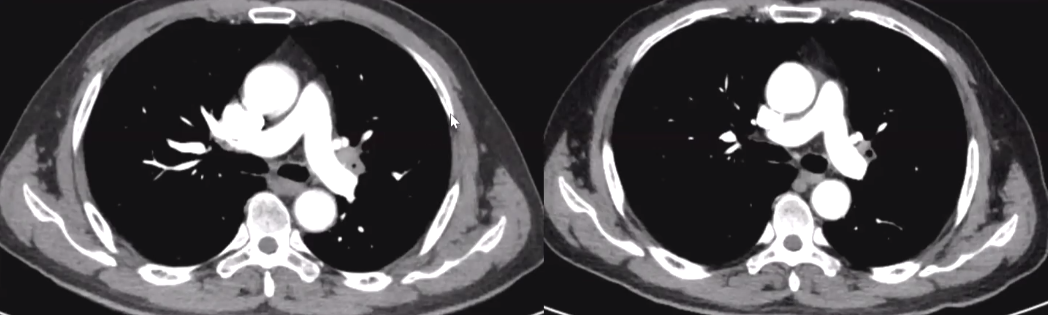

行胸部CT检査示:左肺下叶阴影,伴支气管截断。Bbw帝国网站管理系统

外院CT如下:支气管截断,左肺下叶支气管受侵。Bbw帝国网站管理系统

PET-CT,左肺下叶肿块,FDG代谢增高,符合肺癌表现,伴左肺下叶局限性阻塞性改变左肺门、食管旁(8)、主肺动脉窗(5)、血管前(3A)多发淋巴结,FDG代谢增高,考虑淋巴结转移,结果提示左肺下叶占位为恶性。

初步诊断 IIIA期局晚期左下肺癌

第一周期结束后,复查胸部CT示:左肺下叶支气管阻塞较前减轻,活动后气短症状较前轻度好转。

值得注意的是,术前PET-CT提示:同侧肺门及纵膈淋巴结转移(N2),经两周期新辅助免疫治疗联合化学治疗后。

手术切除标本病理提示:同侧肺门及纵膈淋巴结阴性(NO)尽管术前无淋巴结活检病理,仍可大胆推断,病理降期效果明显。